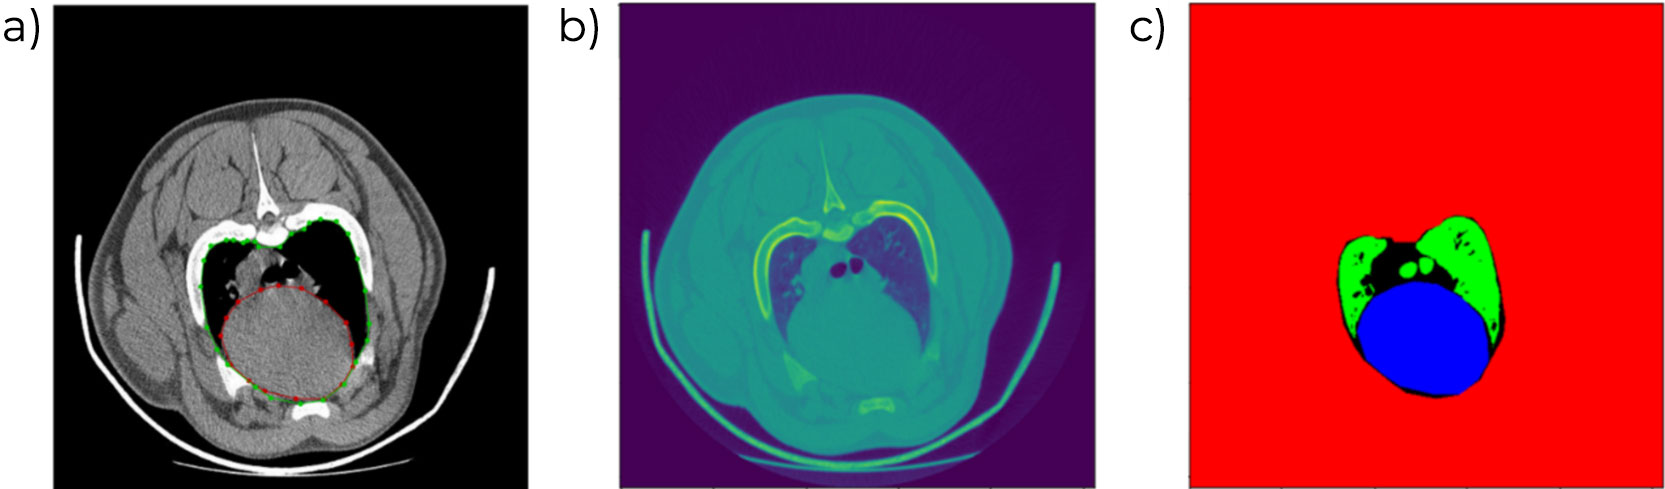

Sự hiện diện của tổn thương ở đầu xương đùi và xương cẳng tay để xác định tình trạng viêm khớp hoặc bệnh loạn sản sụn (osteochondrosis). Đánh giá này được đưa vào mục tiêu chọn lọc của tất cả các dòng di truyền. Quy trình hiện tại vẫn bao gồm bước đánh giá thủ công, nhưng trong tương lai gần sẽ được thay thế bằng quy trình tự động hóa, cho phép phân tách và định lượng tổn thương chính xác hơn, đồng thời mở rộng phạm vi đánh giá các bề mặt xương.

Kích thước và hình dạng của xương bả vai cũng đã được đánh giá và chứng minh có mối tương quan với tuổi thọ của heo nái, cũng như sự xuất hiện của vết loét hoặc các tổn thương khác ở vùng vai của heo nái trưởng thành.